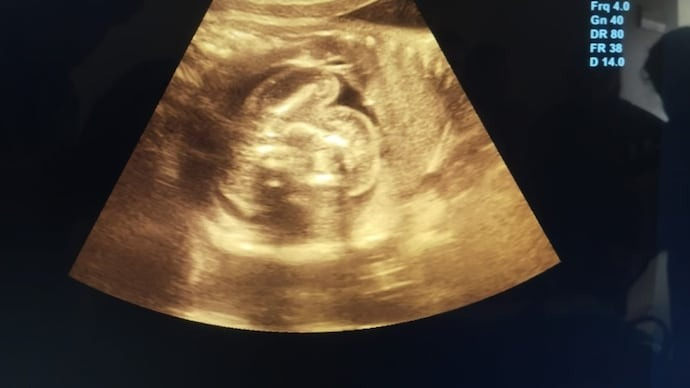

Upon arriving at the hospital, Emma was admitted for monitoring. While reviewing her latest ultrasound, doctors noticed something unusual: a second, smaller amniotic sac adjacent to the main one. Confused and intrigued, the medical team prepared for what they assumed was an unusual presentation of twins.

As the delivery began, doctors carefully navigated the birth of Emma’s healthy baby girl. However, what followed next left the entire team stunned. Inside the secondary sac was what appeared to be an underdeveloped fetus that had stopped growing early in gestation.

This rare occurrence, known in medical terms as “fetus in fetu,” happens when a twin embryo is enveloped by its sibling during the early stages of pregnancy. The enveloped fetus does not develop fully and typically remains undetected unless it causes complications or is discovered incidentally.